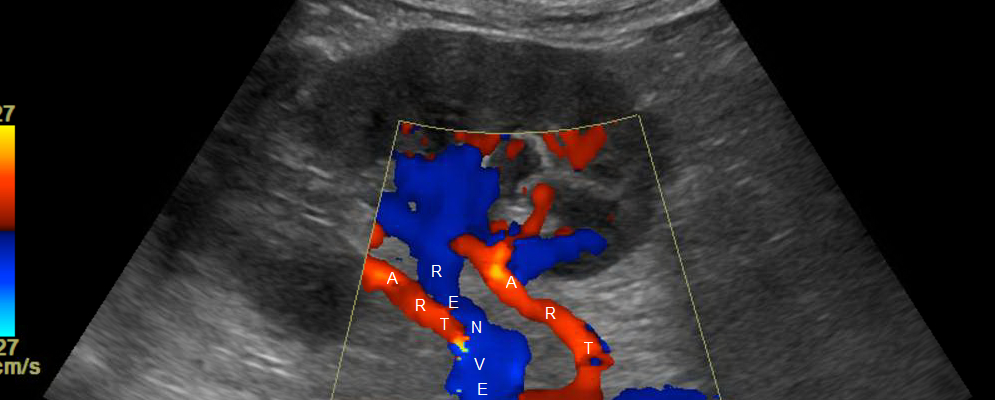

Enter the Renal Artery Colour Doppler—a revolutionary diagnostic tool that offers a non-invasive, yet highly effective means of early detection of renal artery conditions. This technology utilizes sound waves to create detailed images of the renal arteries, allowing healthcare professionals to assess blood flow and detect blockages or narrowing of the arteries swiftly and accurately.

Imagine the relief and empowerment in Rajesh’s life when, during a routine check-up, his doctor recommended a Renal Artery Colour Doppler test after noticing fluctuating blood pressure readings. Within a short span, the test revealed a significant narrowing in one of Rajesh’s renal arteries, a discovery that enabled timely medical intervention. With lifestyle adjustments and medication, Rajesh could manage his condition effectively, preventing further deterioration of his kidney function.